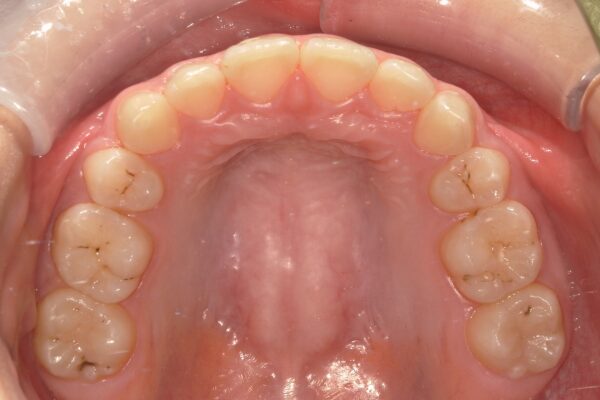

【治療結果】

・著大だったオーバージェット(前歯の突出)が完全に解消され、良好な被蓋関係(咬み合わせ)を獲得しました。

・突出していた口元が下がり、バランスの取れた良好な側貌(横顔)が得られました。

・スペース不足で生えてこなかった下顎の7番も、正常な位置へと誘導することができました。

本症例のように、ガタガタが少ない上顎前突は「抜歯スペースの閉鎖=すべて歯の移動」となるため、通常は治療期間が長引く傾向にあります。 今回、予定より早く良好な結果を得られたのは、患者さんがエラスティック(ゴム)の使用を熱心に協力してくださったことはもちろん、摩擦の少ない「フルパッシブ矯正」による動きの迅速さが大きく影響していると考えています。